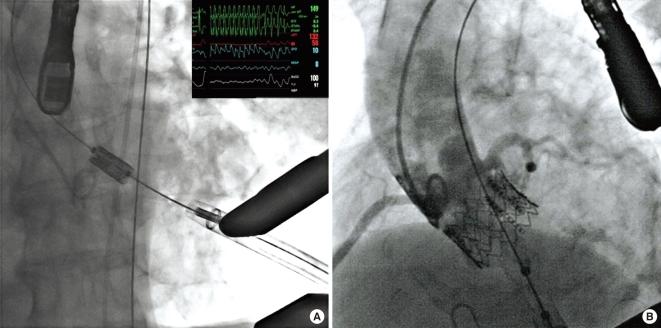

The first successful transapical aortic valve implant in Korea.

Transcatheter aortic valve implantation is an alternative to open heart surgery in high risk patients with severe aortic stenosis. High mortality and complications related to cardiopulmonary bypass for conventional open heart surgery can be avoided with this new less invasive technique. In case of concomitant severe arterial disease, the transapical approach is recommended rather than transfemoral access. An 80-yr-old man with symptomatic aortic stenosis and who had very high surgical risk factors such as diabetes mellitus, hypertension, a history of stroke, bronchial asthma including poor pulmonary function and hepatocellular carcinoma was treated with a transapical aortic valve replacement. The expected mortality in this patient was 25.4% by Euroscore if we performed the conventional aortic valve surgery. The patient was discharged and was well at the 45 follow-up days. We report the first case of successful transcatheter transapical aortic valve implantation which is available recently in Korea.